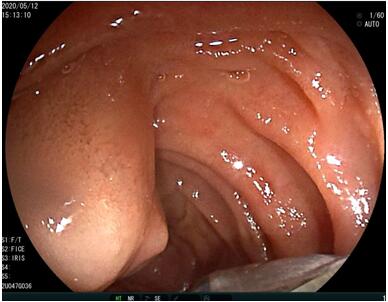

69歲王姓患者,因“發(fā)現(xiàn)無(wú)痛性黃疸1月”入院,根據(jù)患者病史,患者診斷傾向于壺腹部腫瘤所致梗阻性黃疸。予以完善腹部CT及上腹部MRI加MRCP均顯示肝內(nèi)外膽管擴(kuò)張,未發(fā)現(xiàn)明顯膽管,胰腺及十二指腸乳頭部腫瘤,且患者CA199正常。以前醫(yī)院未引進(jìn)超聲內(nèi)鏡,這類患者到此就遇到診斷瓶頸。此患者經(jīng)過消化內(nèi)科張丹霞副主任醫(yī)師完善超聲內(nèi)鏡檢查后,可以清楚顯示膽總管下段壁內(nèi)軟組織占位?;颊咄ㄟ^超聲內(nèi)鏡檢查診斷明確,轉(zhuǎn)至肝膽外科行手術(shù)治療。

上腹部MRI圖片